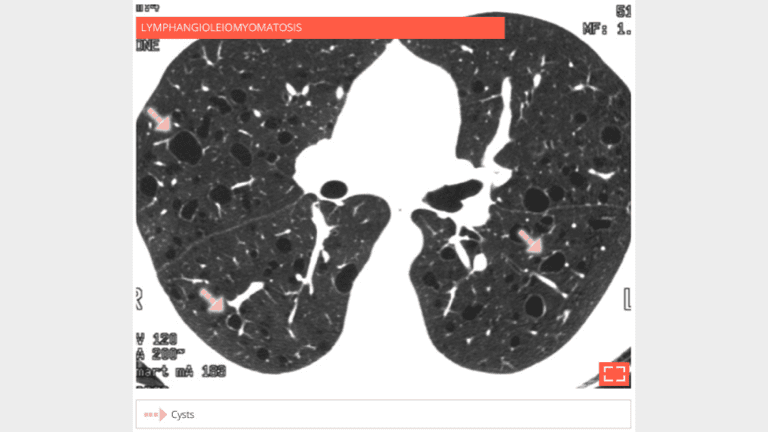

HRCT shows multiple cysts throughout the lung parenchyma in a young female patient. Note that the adjacent lung is unremarkable.